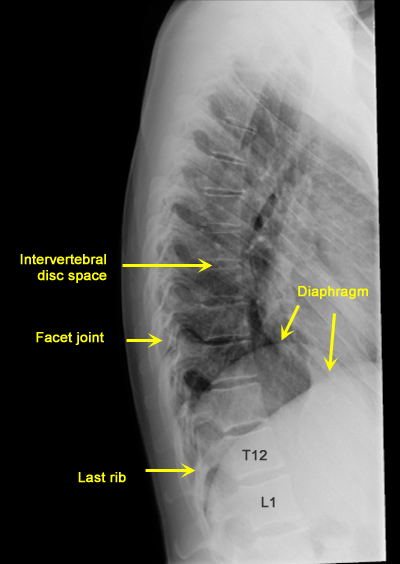

Plain Films of Skull and Spine